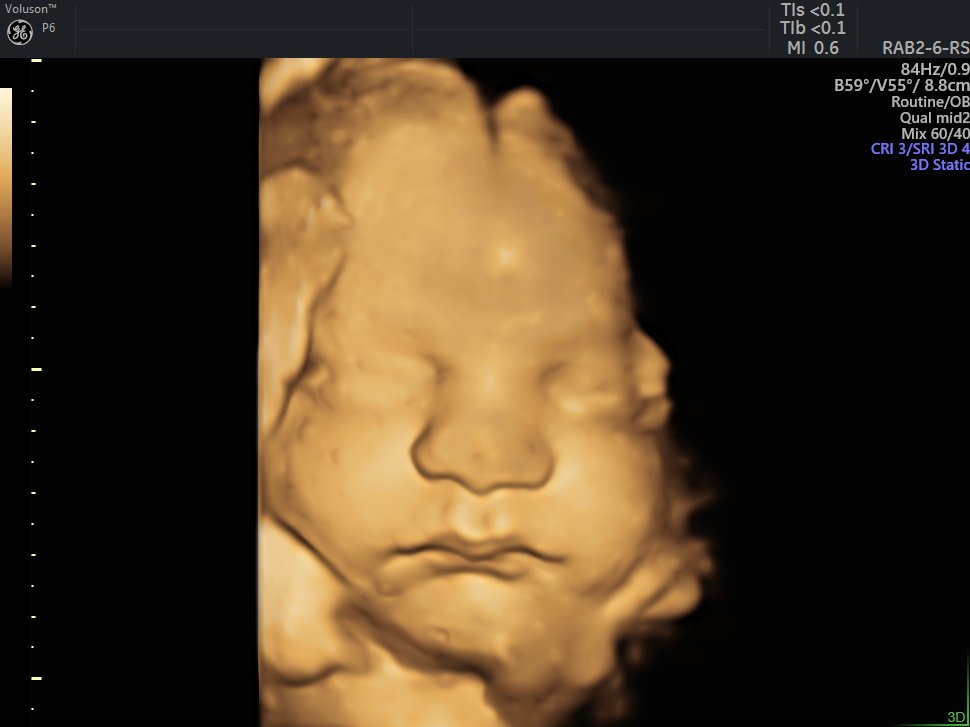

4 D Ultrasonografi

4 Boyutlu (Renkli) Ultrason ve Doppler Ultrasonografi